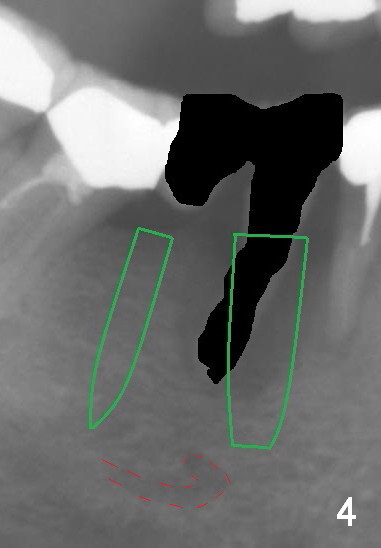

A 50-year-old lady (ZC) has poor dentition (Fig.1). The buccal gingiva of the tooth #29 is erythematous and edematous with deep pockets and severe bone resorption (Fig.2). Two units of the 5-unit bridge is going to be removed (Fig.3). A large implant is to be placed at the site of #29 (socket treated with Metronidazole), while a small one (probably 1-piece) at #30 (narrow mesiodistal space, Fig.4 green outlines). Be care of the mental loop (red dashed line). In fact, the patient wants to have #3 implant placed first.